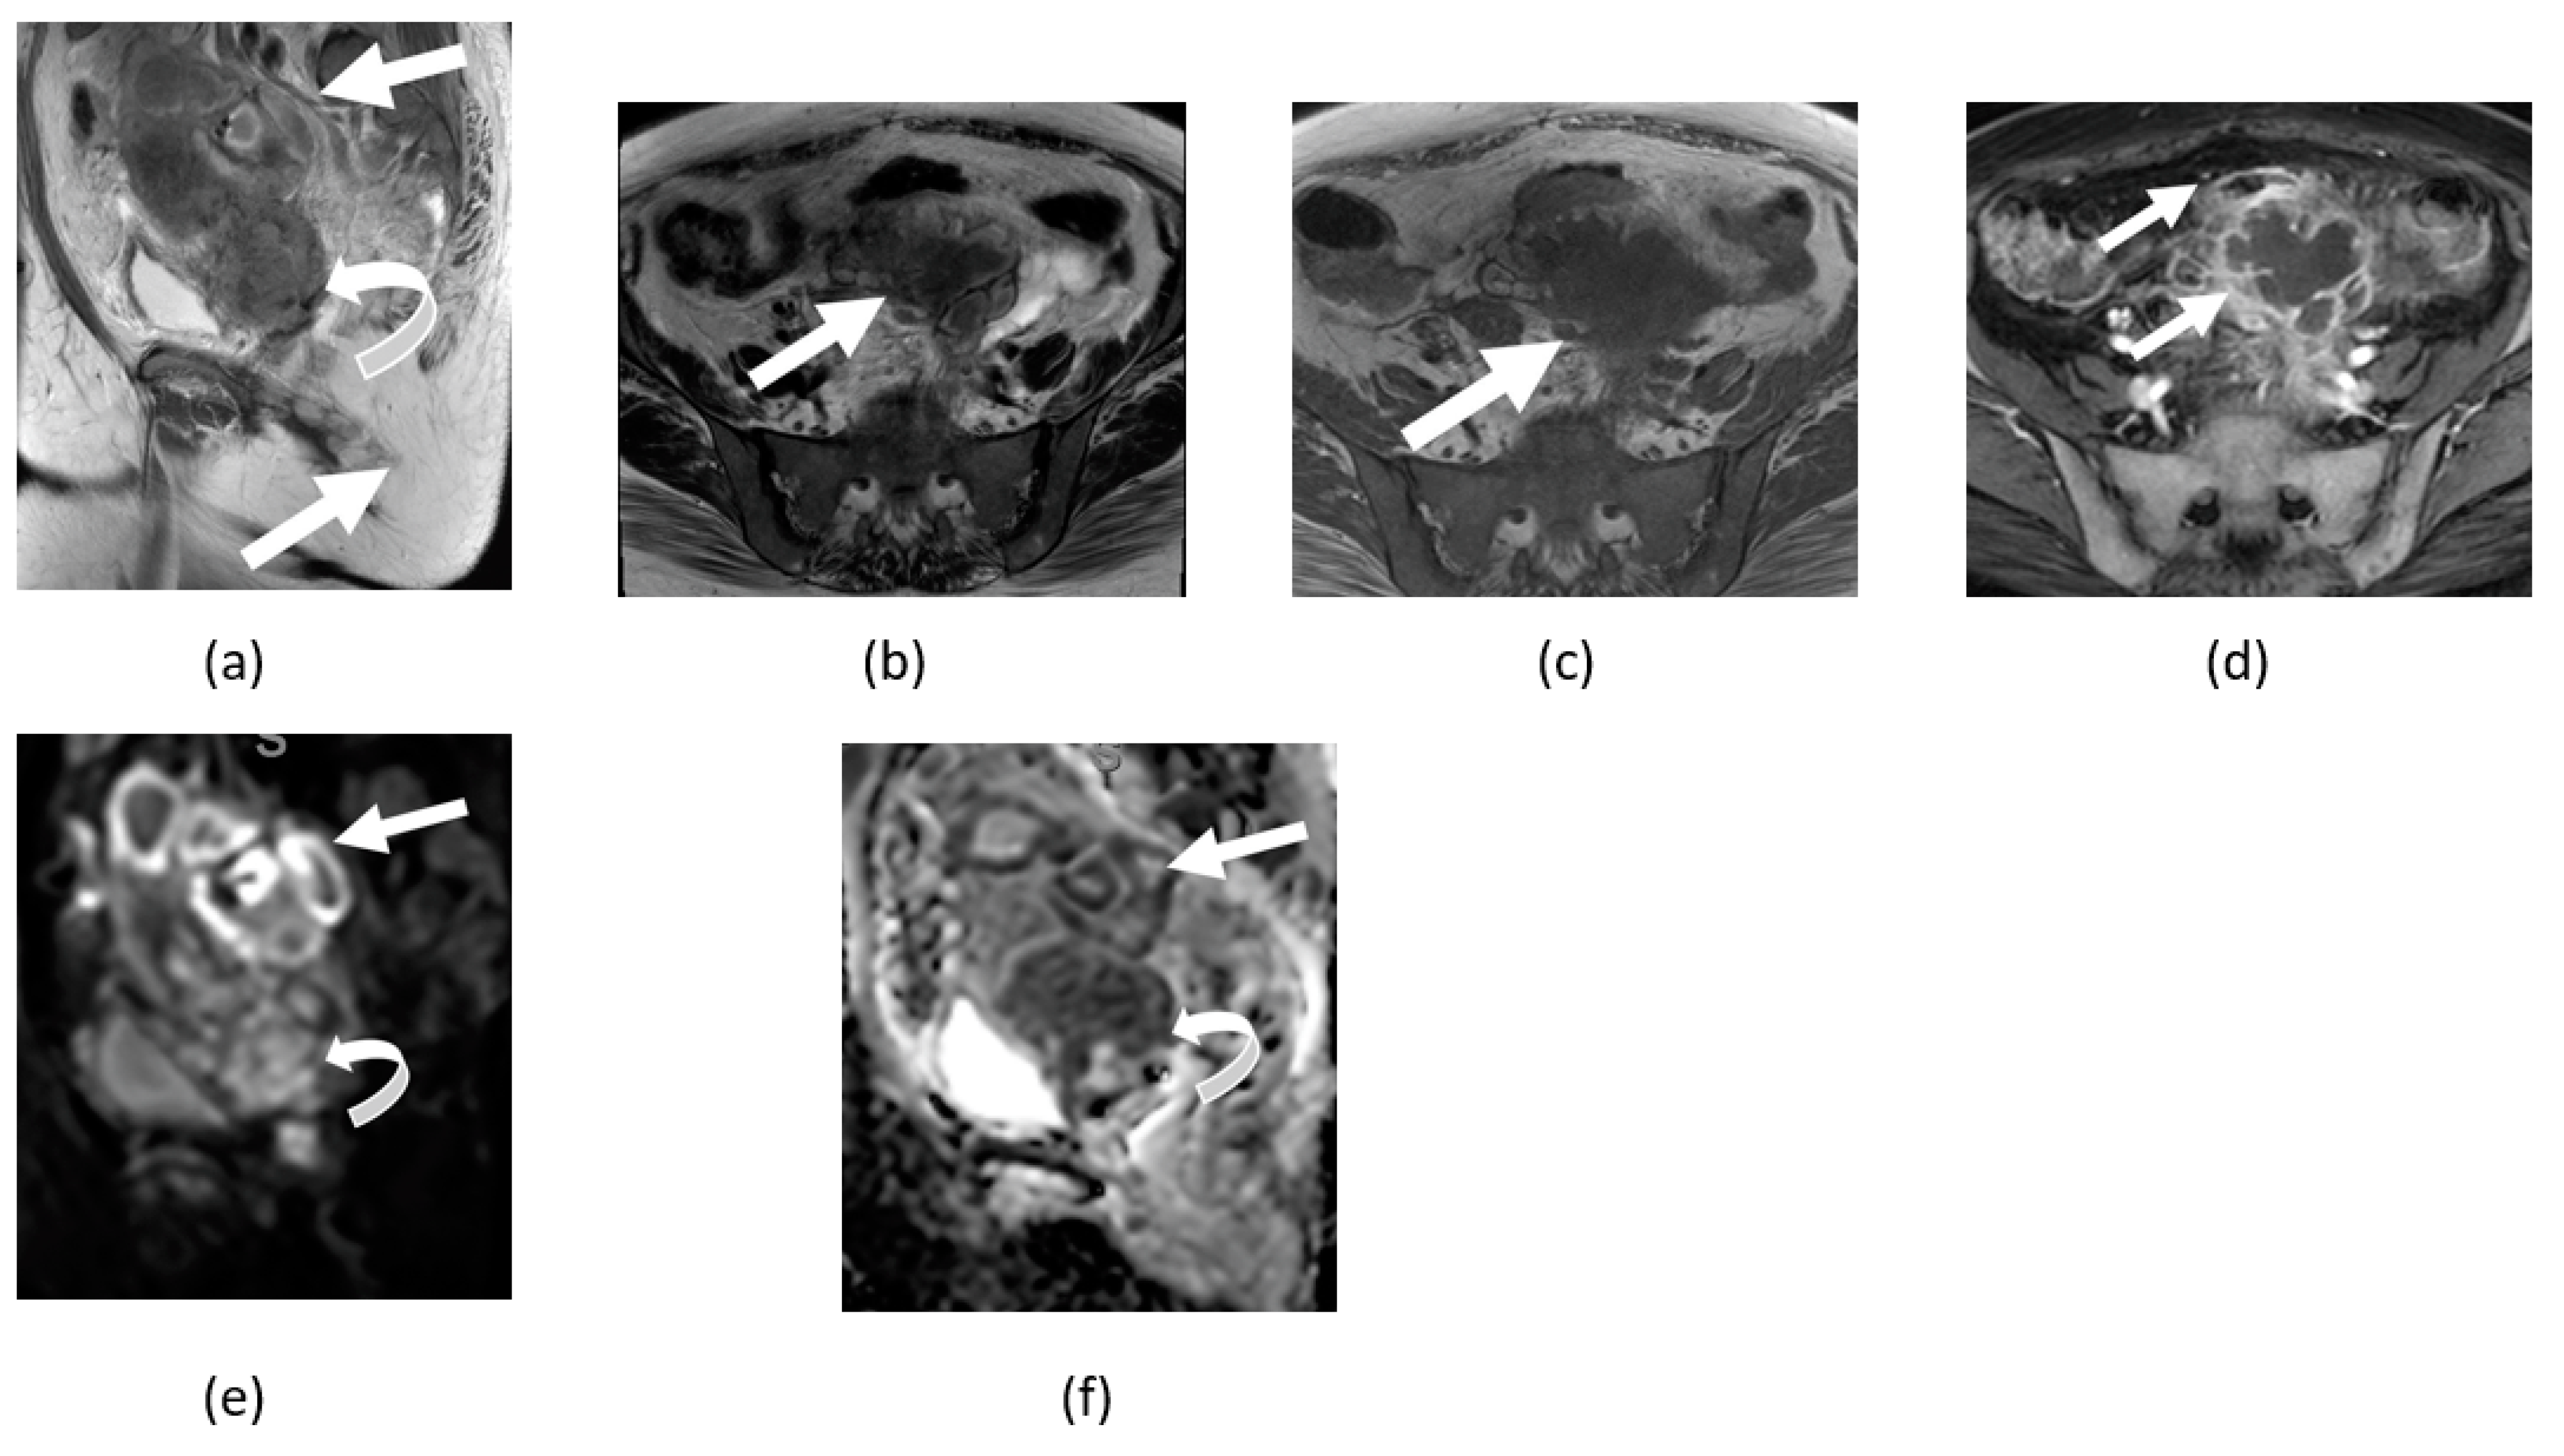

3.3. Endometriosis

3.4. Tubo-Ovarian Abscess